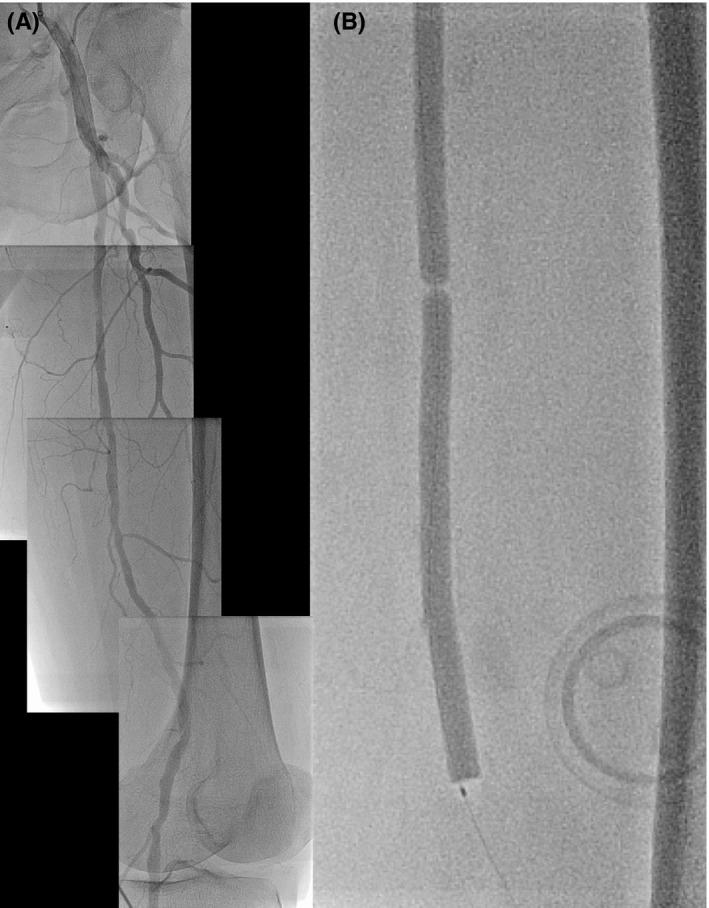

Paclitaxel-coated balloons have demonstrated improved efficacy compared with uncoated percutaneous transluminal angioplasty for femoropopliteal artery disease. While applying a long balloon, twisting of the balloon can be occurred. We reported two cases with twisting of the Ranger drug-coated balloon for treating superficial femoral artery.

与未涂层的经皮腔内血管成形术相比,紫杉醇涂层球囊已证明在治疗股腘动脉疾病方面疗效更佳。在使用长球囊时,球囊可能会发生扭转。我们报告了两例使用Ranger药物涂层球囊治疗股浅动脉时发生球囊扭转的病例。